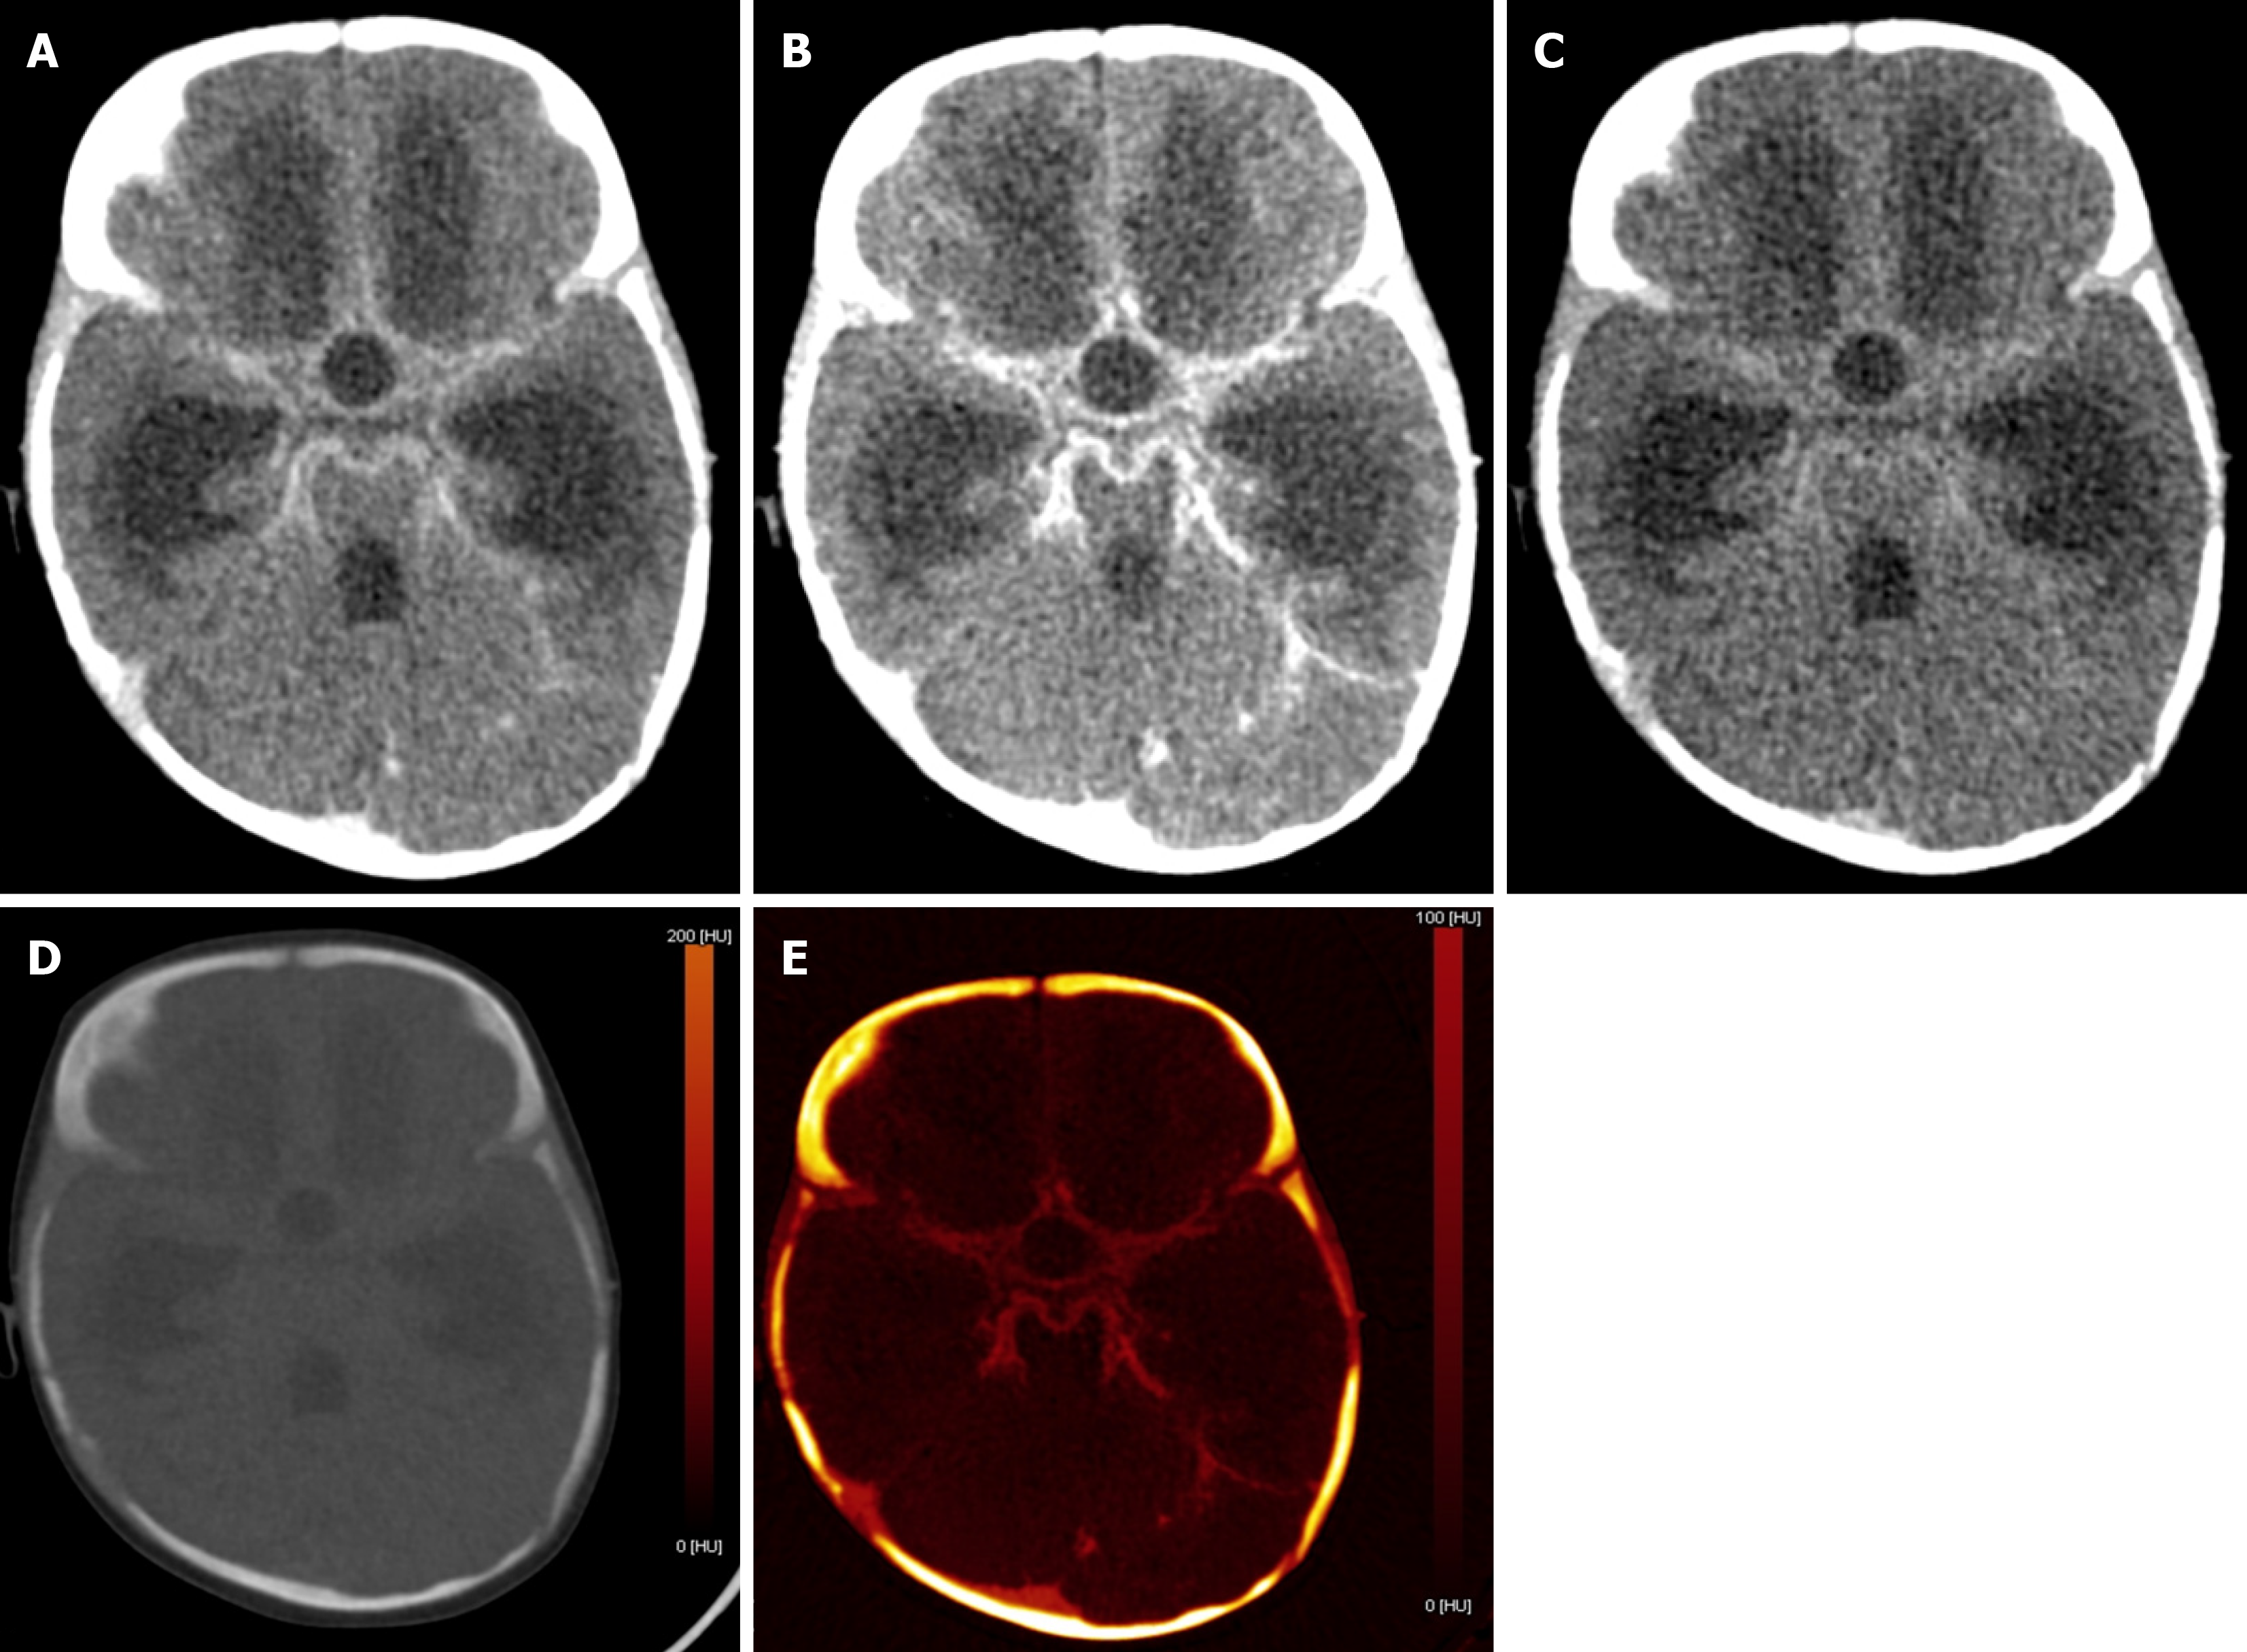

Figure 6 A 7-month-old female with fever and abnormal body movements, suspected of having either a bleed or meningoencephalitis.

A: Axial blended contrast enhanced image showed abnormal leptomeningeal enhancement; B: Image at 70 kV showed marked increased contrast with increased conspicuity of the abnormal enhancement; C: Image at 150 kV showed decreased noise but at the cost of poor contrast; D: Virtual non-contrast image ruled out any abnormal bleed; E: Iodine-specific image showed iodine uptake in the region of hyperdensity, adding to the confidence in the diagnosis of meningitis.